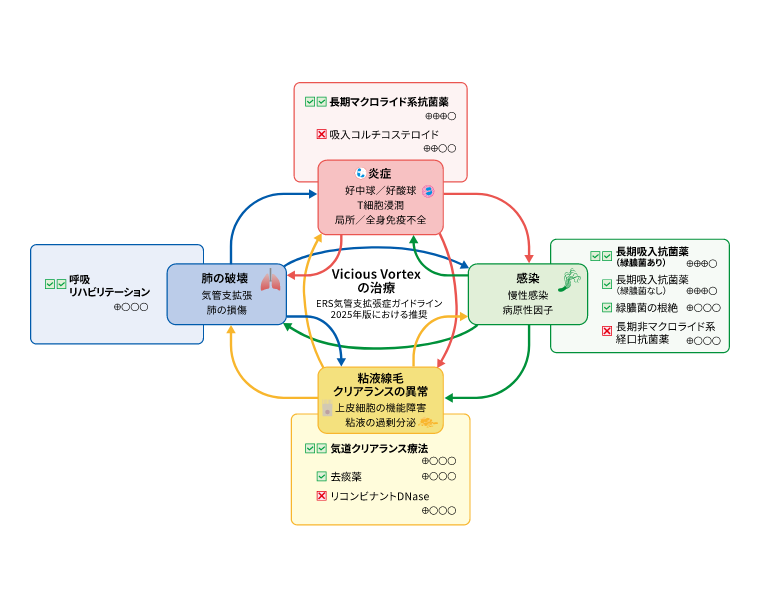

病態

治療

ガイドライン